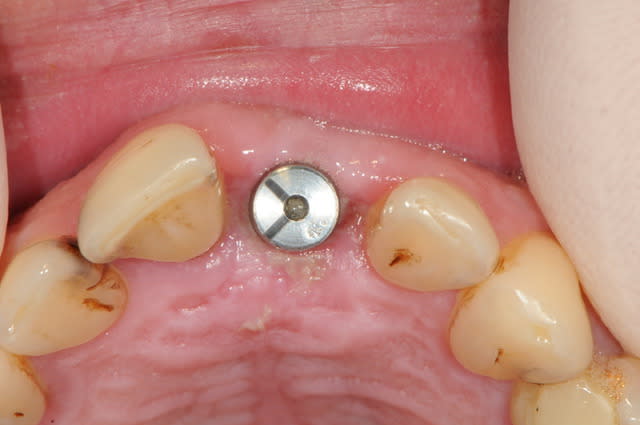

Un pilier de cicatrisation customisé ou personnalisé c'est une vis de ciatrisation individualisée : elle peut être faite de plusieurs facons par exemple à partir de ton porte implant que tu modifies par apport successif de composite.

Ca ressemble à cela :

une fois positionnée en bouche, je remet la courone sur le pilier que je démonte et réalise l'émergence avec le flow.

ici, c'est un implant AXIOM, le diamètre à la sortie du col de l'implant est très fin (cône et platform switching) et permet donc de travailler l'émergence au mieux.

je dis cela car sur les autres type d'implants avec une connexion plate, l'utilisation d'un pilier personnalisé est plus souvent nécessaire.